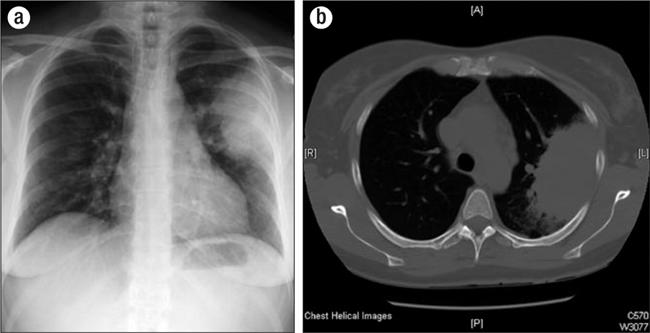

Physical examination revealed an ill-appearing patient. She had mild bibasilar crackles in her lungs. Her vital signs and results of the remaining physical examination were normal. Laboratory tests obtained in the emergency department are shown in Table 1. A radiograph and computed tomography (CT) scan of her chest revealed a large confluent density in the periphery of the left midlung and two smaller nodules in the right midlung as well as multiple reactive mediastinal lymph nodes (Figure 1). A peripheral blood smear showed hypochromasia, polychromasia, and rouleaux.

Figure 1.

(a) Chest radiograph showing a confluent density in the left midlung and two smaller pulmonary nodules in the right midlung. (b) Computed tomography scan showing the same nodular findings with the addition of mediastinal lymphadenopathy.